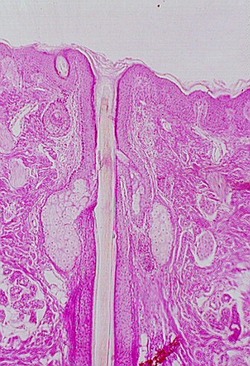

Look at hair follicles in your slide of thin skin (Slide 24). Hairs are also found in the hypodermis growing up into the dermis. Each hair arises from an epidermal invagination, the hair follicle, that teminates in a dilation called the hair bulb. Find these structures in the following photographs.

hair follicle with hair inside the shaft. In the left hand photo, 18) identify har bulb,

follicle epithelium. The dermal papilla can't be seen well, however you can find one in

your slide set. The right hand photo shows the hair going up to the epidermis. You can see

the hair follicle as an invagination of the epidermis. Another view of the follicle is

shown below.